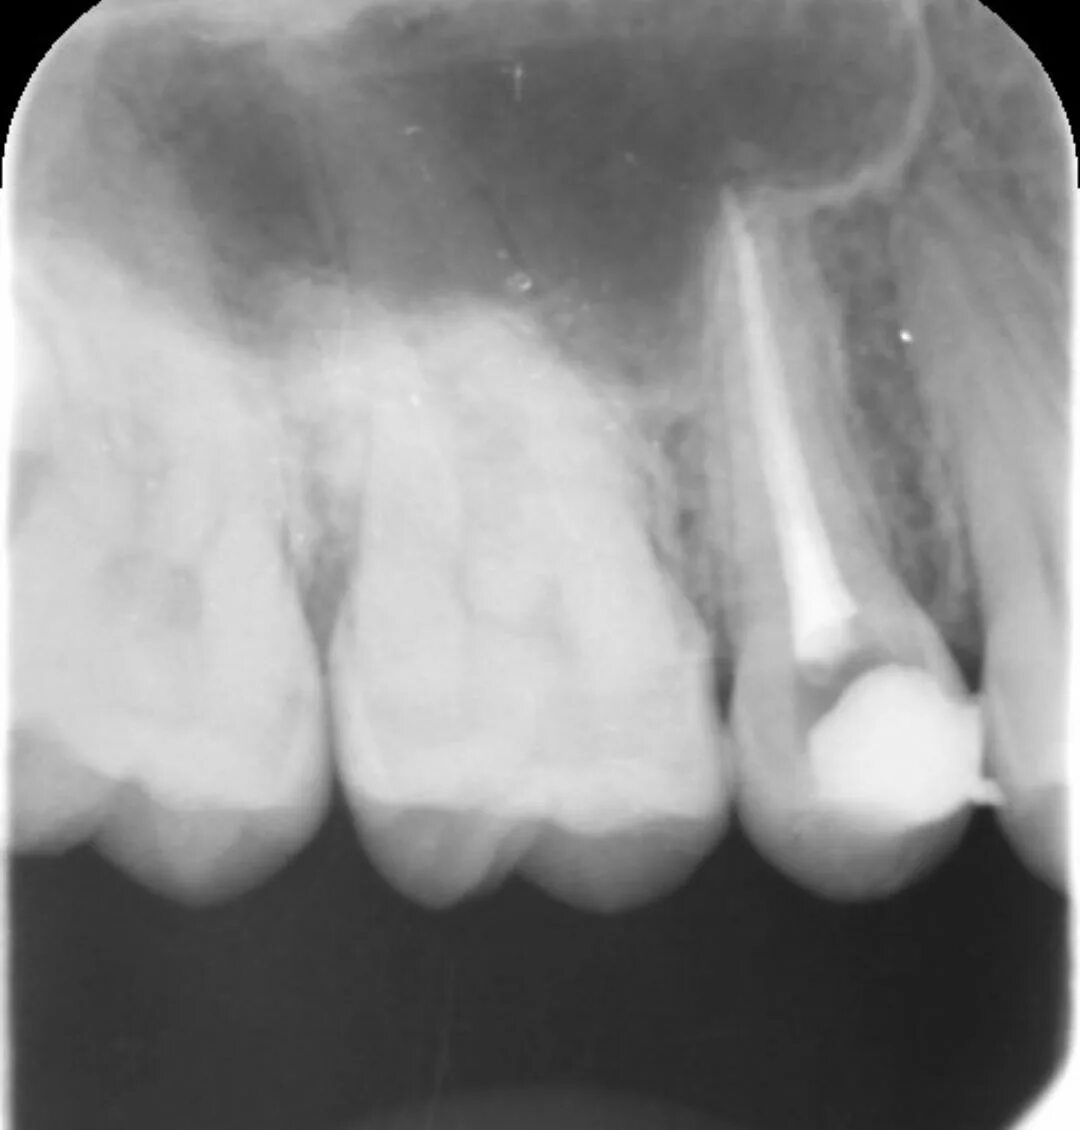

Удалить нервы запломбировать